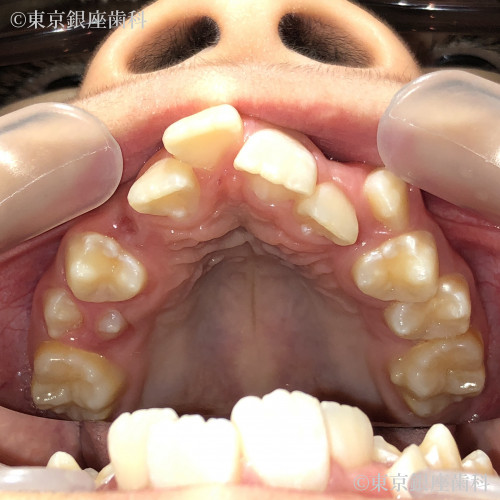

Before

10代 女性

疾患 矯正

施術内容 矯正

治療期間 11ヶ月 費用 65万円(税込)

インビザライン:ファースト